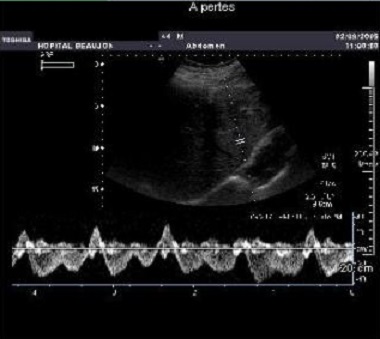

Les veines sus-hépatiques sont bien visualisées par coupe

hypochondre droit axial oblique. Leurs parois sont fines et

régulières et en pratiquement a trois branche . Le flux

sanguin est triphasique reflet du cycle cardiaque et tres

sensible a inpiration force .

La veine porte présente un diamètre antéropostérieur

normalement inférieure à 12 mm en respiration spontanée. Son

diamètre varie moins au cours de la respiration que celui

des veines sus-hépatiques. Ses parois sont bien visibles.et

sa flux sanguine est mono-phasique a nombreuse de frequence

representees . Normalement sa vitesse moyene > 10mm/s et

vitesse max est de > 18mm/s

Le flux sanguin de veine sus hepatique

est triphasique , reflet du cycle cardiaque et tres

sensible a inpiration force . |

La flux sanguine de veine porte est mono-phasique

avec de nombreuse de frequence representees .

Normalement sa vitesse moyene > 10mm/s et vitesse

max est de > 18mm/s |